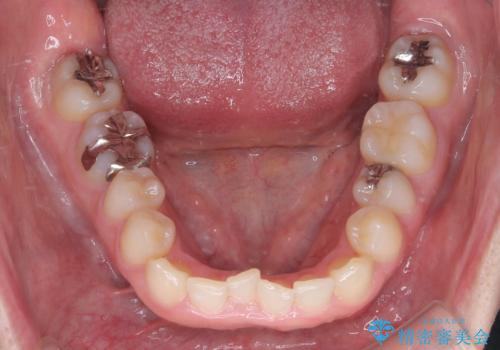

- 前歯の叢生(ガタつき)と、上下の噛み合わせが一部逆になっている反対咬合を主訴にご来院されました。精密検査の結果、前歯の移動だけでは不十分で、歯列全体のアーチを整えながらスペースを確保する必要があると診断。

中等度の症例に最適で最大26ステージ(※プランによる)のマウスピースが使用可能な**「インビザライン・モデレート」**を選択しました。これにより、抜歯をせずに歯列を横に広げ(側方拡大)、前歯を並べる十分なスペースを作りながら反対咬合を確実に改善する計画を立案しました。

反対咬合の解消: 内側に入っていた前歯を、マウスピースの力を利用して外側へ押し出しました。同時に、下顎の歯並びも微調整することで、スムーズに正常な噛み合わせへと誘導しました。